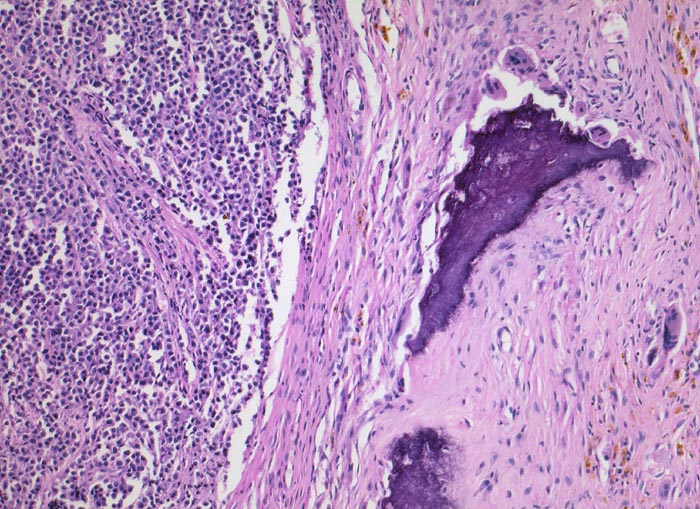

Knochenmarkstanze mit nodulärer Hyperzellularität des blutbildenden Marks.

Keine wesentliche Osteopenie.

In den hyperzellulären Arealen dichte Rasen neoplastischer atypischer Plasmazellen.

Ausserhalb der Plasmazellrasen findet sich spärlich residuelles blutbildendes Knochenmark.